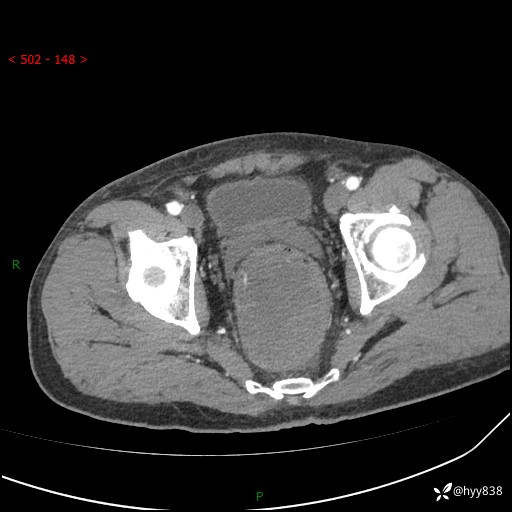

盆腔CT平扫+增强